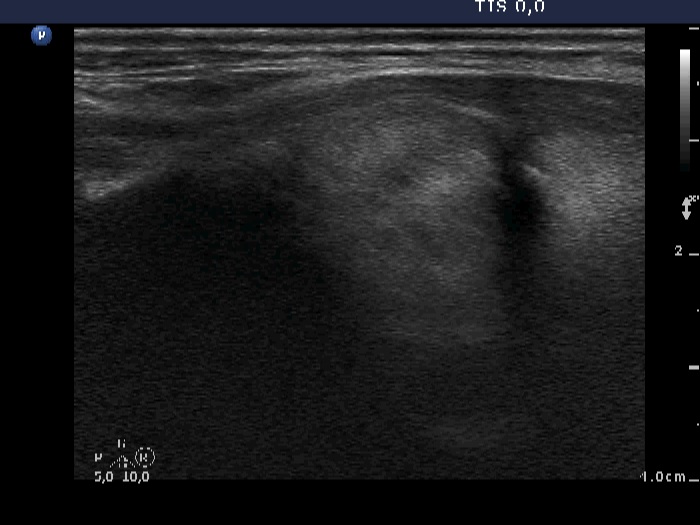

Ethanol sclerotherapy: non-toxic solid nodules - Case 5

Twelve years after the therapy (ultrasonographic picture 5)

Upper part of the left lobe, longitudinal scan.